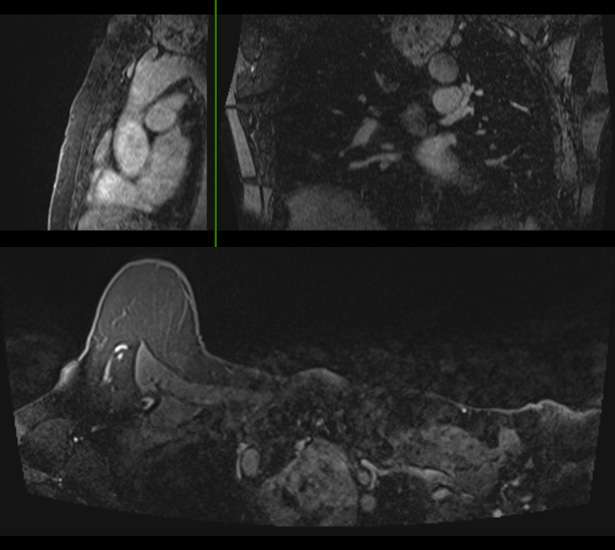

- Patients with pulmonary artery hypertension (Figure 2) may require additional clinical evaluation for underlying factors such as chronic obstructive pulmonary disease or congestive heart failure.

Incidental thyroid nodules should undergo additional imaging with thyroid ultrasound if they meet criteria per guidelines from the American College of Radiology. Thyroid ultrasound is indicated in patients younger than 35 years of age with incidental thyroid nodules measuring greater than 1.0 cm and in patients older than 35 years of age with incidental thyroid nodules measuring greater than 1.5 cm (6). Thyroid nodules should also be evaluated with additional imaging if they demonstrate suspicious features such as abnormal morphology or invasion into adjacent tissue. For example, this patient with an incidental superior mediastinal mass was recommended to undergo chest CT and/or thyroid ultrasound (Figure 3).

Figure 3. 91-year-old patient with a history of left breast mastectomy with incidental heterogeneously enhancing mass within the superior mediastinum and with rightward tracheal deviation. Recommendation for chest CT and/or thyroid ultrasound was made to further characterize the extent and invasiveness of the lesion.- It is important to identify incidental findings on breast imaging and stratify which require additional imaging, as these may have implications for patient care.